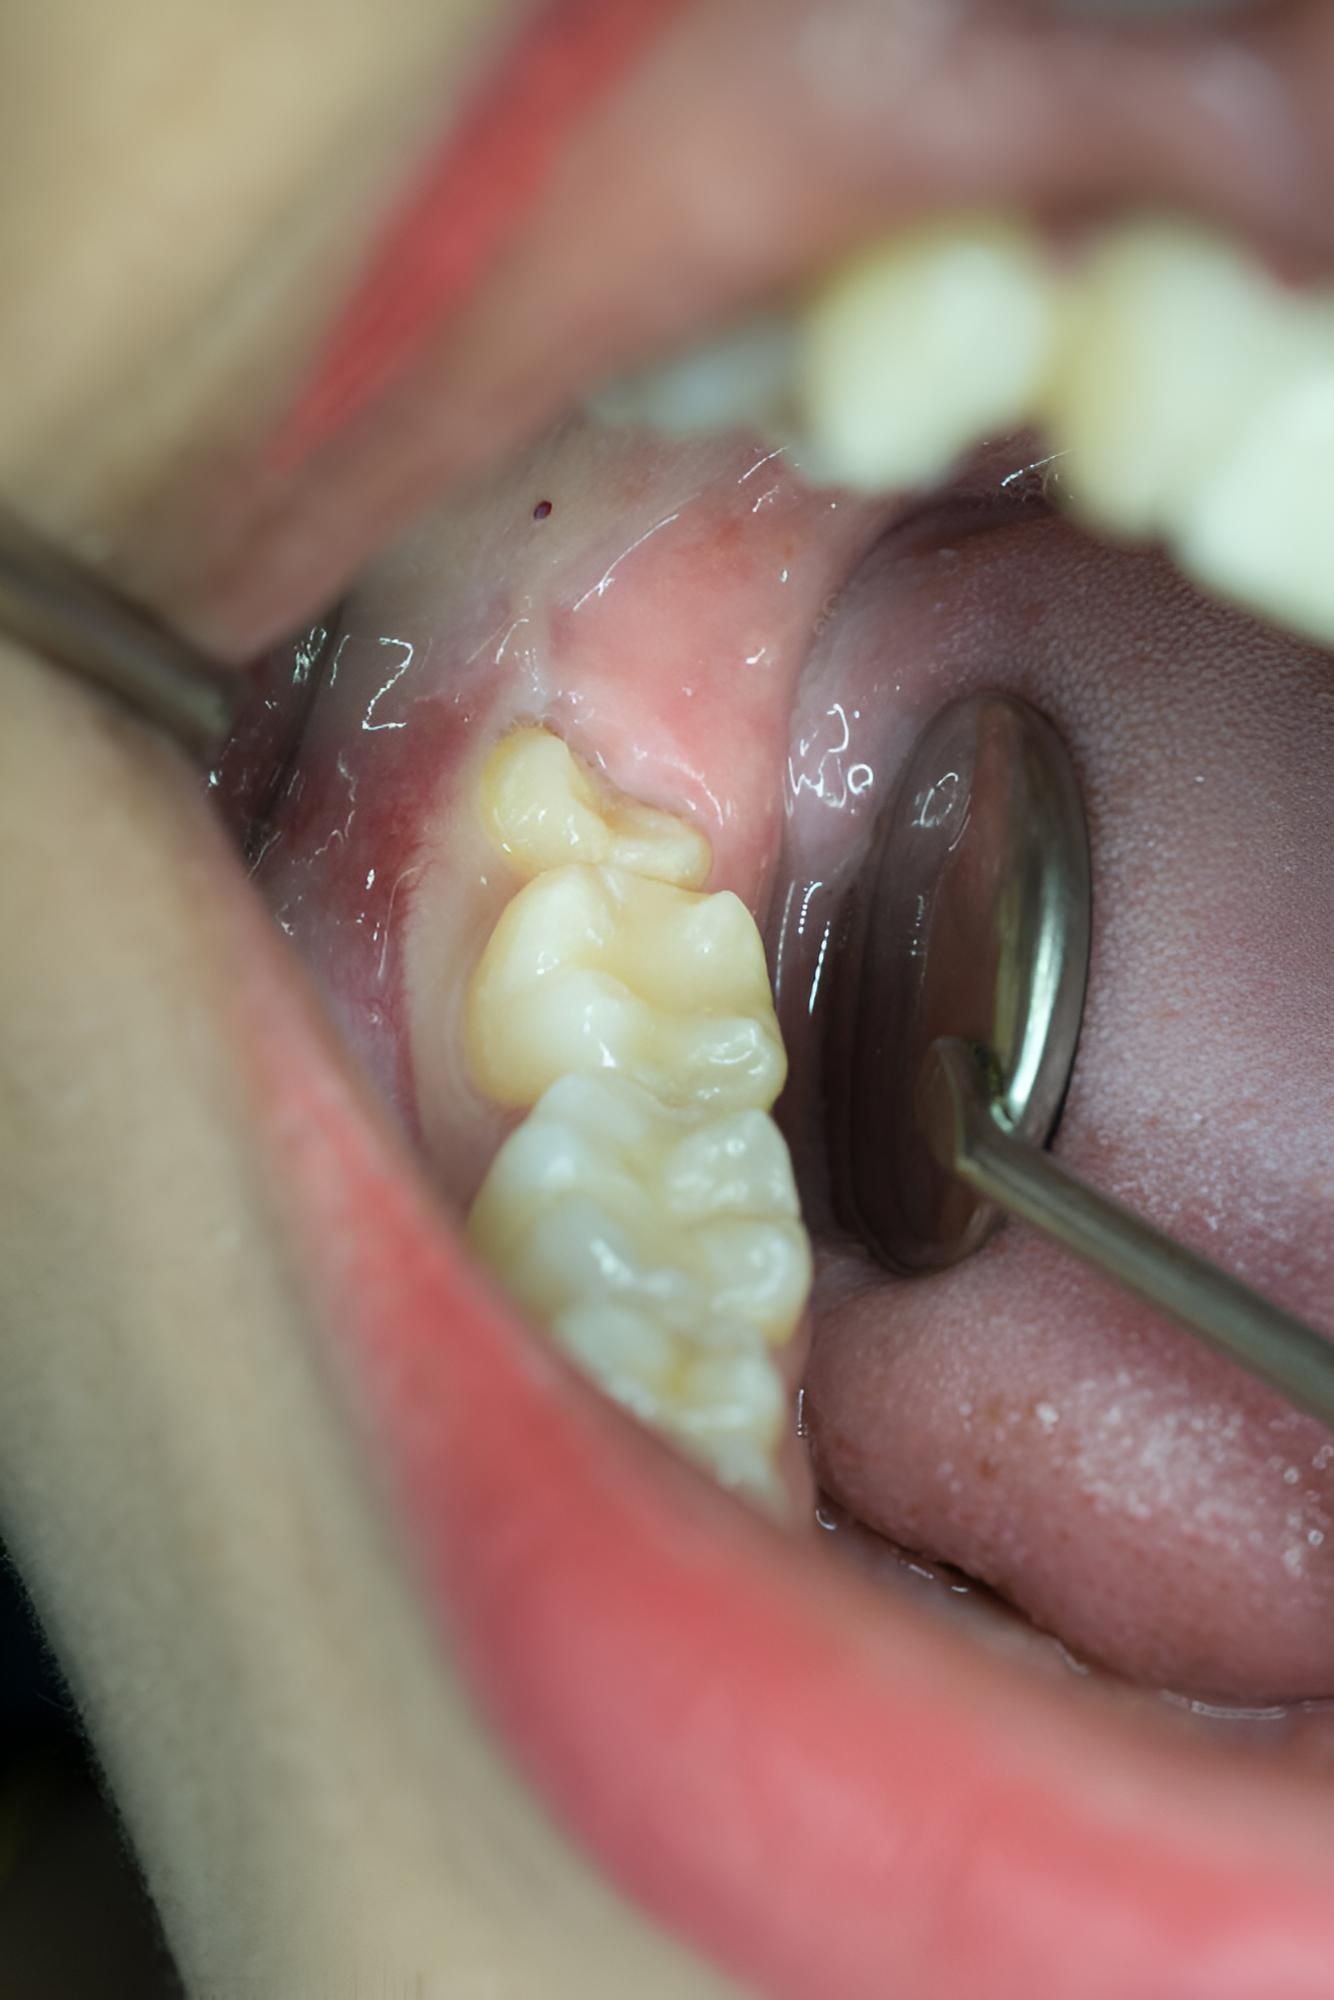

- Impacted Growth: When wisdom teeth grow at odd angles or get stuck below the gum line, they can cause pressure and pain.

- Recurring Infections: Partially erupted wisdom teeth are hard to clean and can trap bacteria, leading to gum infections.

What is an impacted wisdom tooth?

An impacted wisdom tooth is one that fails to fully emerge through the gum or grows in at an angle due to lack of space. This can cause pain, swelling, and lead to infections or damage to nearby teeth. In some cases, cysts can form around the impacted tooth. Impacted wisdom teeth are usually discovered during dental checkups and are commonly removed to prevent further complications and support the long-term health of surrounding teeth and gums.